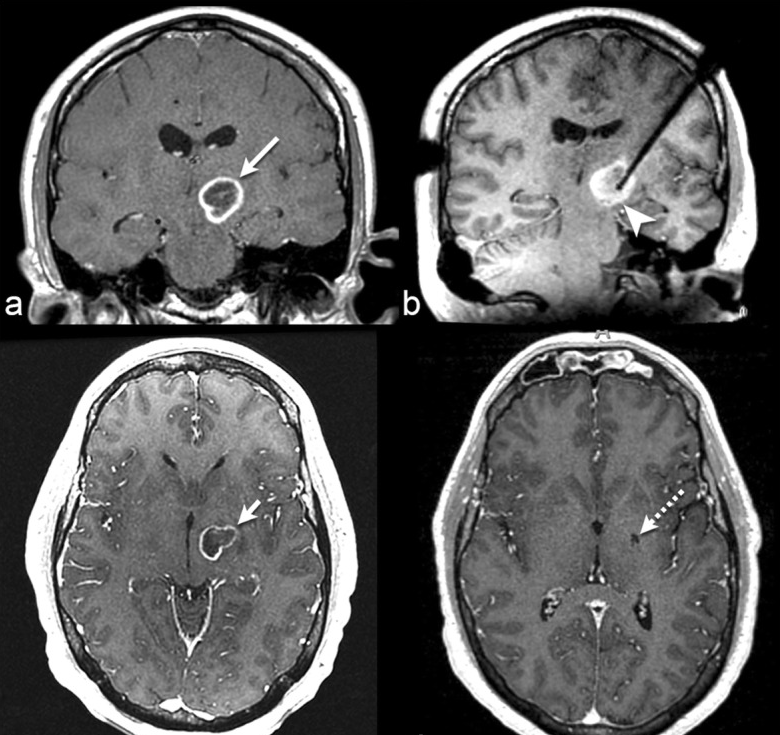

2015年,Banerjee等人回顾了神经肿瘤学中磁共振成像引导的磁共振成像引导的磁共振成像引导的磁共振成像引导的磁共振成像引导的磁共振成像引导的磁共振成像引导的磁共振成像引导的磁共振成像引导的磁共振成像引导的磁共振成像引导的磁共振成像引导的磁共振成像引导的磁共振成像引导的磁共振成像引导的磁共振成像引导的磁共振成像引导的磁共振成像引导的磁共振成像引导的磁共振成像引导的在复发的ⅲ/ⅳ级胶质母细胞瘤患者中,他们发现,与给予其他治疗方案的患者相比,在20.9个月时,采用LITT治疗的患者从复发诊断中获得的总中位生存期有所好转。未来的前瞻性研究需要准确评估原发性脑肿瘤患者的预后。我们提供了一个脑转移患者的例子,他使用LITT成功地进行了治疗(图1)。

图1:35岁,活检证实左丘脑胶质母细胞瘤。LITT前冠状核磁共振造影后t1加权成像显示环状强化肿块(长箭头)。b冠状面术中定位t1加权MRI显示肿物内的激光探针(箭头)。LITT术后2.5个月c轴位t1加权造影后MRI显示肿块轻微缩小(短箭头)。LITT后4个月的d轴后对比t1加权MRI显示胶质母细胞瘤完全消退(虚线箭头)